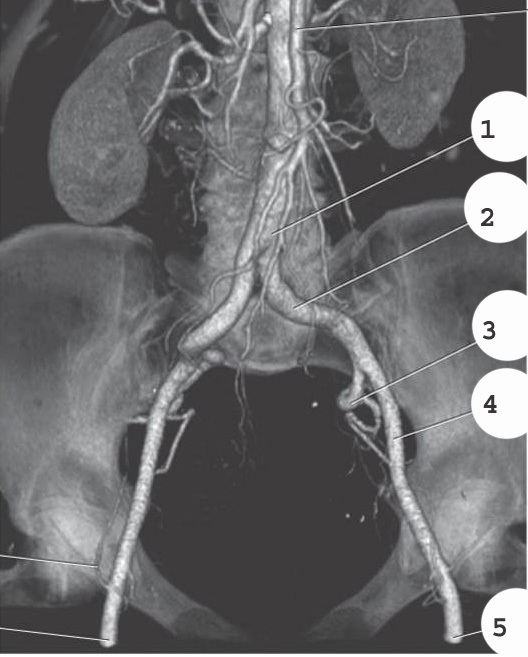

1

popliteal artery

2

anterior tibial artery

3

fibular artery

4

posterior tibial artery